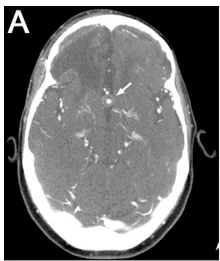

一名37岁男性患者,有右额叶星形细胞瘤病史,该肿瘤在其12岁时确诊,曾接受手术切除及全脑放疗治疗。患者另有药物难治性癫痫病史,曾使用奥卡西平、双丙戊酸钠、左乙拉西坦进行治疗,并植入迷走神经刺激器。在近期一次癫痫发作及创伤性脑损伤后,患者接受头颅CT及CT血管成像随访检查,结果显示其前交通动脉(ACoA)存在一直径5毫米的动脉瘤,伴部分血栓形成及钙化,该动脉瘤原大小为10.3毫米,同时发现右侧脑卒中旧灶(图1A)。

A:术前CT血管成像显示10.3毫米部分血栓形成的ACoA动脉瘤(箭头)。